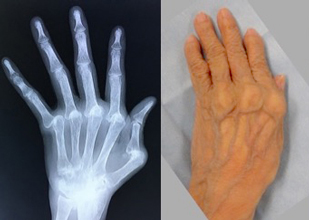

関節リウマチ

リウマチによる手・肘の変形に対する治療は一般的に難易度が高く、また習熟している施設は限られています。当院ではリウマチ手指や肘に対する人工関節手術を積極的に行い、良好な治療成績を得ています。また比較的若年の方で関節面が保たれている場合は可能な限り関節温存手術を行います。当院の担当医はリウマチ指の人工関節手術、人工肘関節手術、人工関節を用いない手指軟部組織形成術や肘関節形成術の経験も豊富です。人工関節は複数の種類がありますが、患者さんの状態に合わせて使い分けています。肩については、変形性関節症のところでも触れている、近年開発された肩の特殊な人工関節(リバース型)が導入されて以降、良好な成績が得られています。